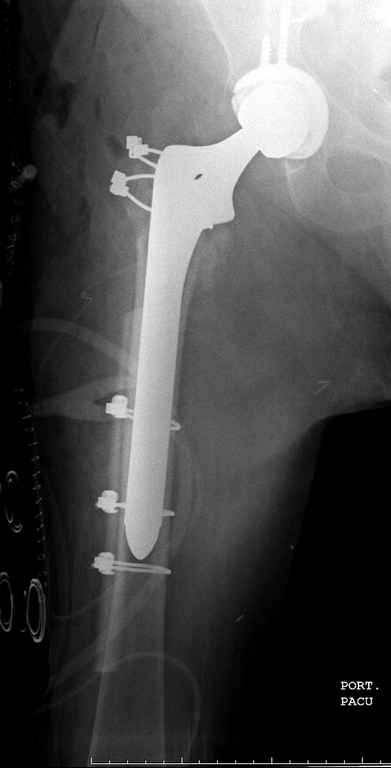

В данном случае в головке бедра и в вертлужной впадине огромный дефект, навряд ли удалением импланта или заменой на другой можно сохранить сустав.

Вашему вниманию представляется похожий случай, пациентке 70, осложнился в течение одного месяца после операции. Ревизия с заменой сустава, кабельная фиксация на трохантер. При установке в дистальном диафизе обнаружен тонкий кортикальный слой и сделана профилактика от возможного перелома аллографтом.